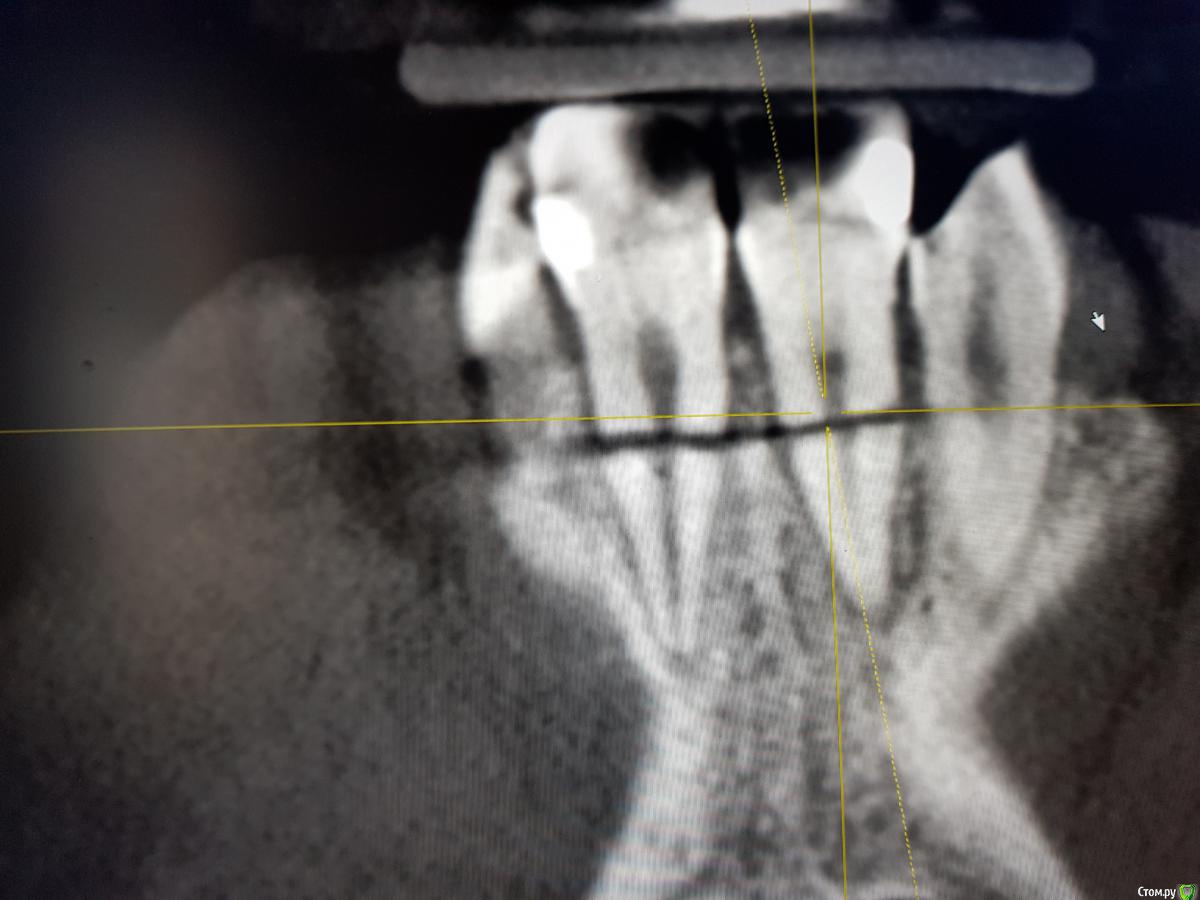

Kazankov.Egor Опубликовано 25 сентября, 2018 Поделиться Опубликовано 25 сентября, 2018 (изменено) Травма, фактура 11,21. Вопрос: одномоментно или отсроченно (НКР в момент удаления). Что смущает в одномоментной постановке:1) как заглубить имплантат, если использовать титановую сетку (поставить ниже уровня зенитов соседних зубов и край верхний край зафиксировать небно, т.е. фактически засыпать их наглухо или фиксировать мембрану от уровня платформы?)2) как это всё ушить правильно.3) те ли вопросы я задаю) Изменено 25 сентября, 2018 пользователем Kazankov.Egor Ссылка на комментарий

Дмитрий Л. Опубликовано 25 сентября, 2018 Поделиться Опубликовано 25 сентября, 2018 Вы видите перелом в.ч. между зубами? Если фрагмент сохранить не удастся, будут большие трудности с сосочком.Когда была травма? Какие жалобы? Status localis? Я за репозицию и шинирование. Ссылка на комментарий

Kazankov.Egor Опубликовано 25 сентября, 2018 Автор Поделиться Опубликовано 25 сентября, 2018 Когда была травма? Какие жалобы? Status localis? Я за репозицию и шинирование. Травма около месяца назад, зубы подвижны (1-2 степень), слизистая бледно-розового цвета, влажная, свищевой ход в области 11 зуба. Ссылка на комментарий